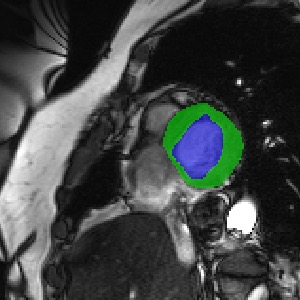

Transformers, the default model of choices in natural language processing, have drawn scant attention from the medical imaging community. Given the ability to exploit long-term dependencies, transformers are promising to help atypical convolutional neural networks (convnets) to overcome its inherent shortcomings of spatial inductive bias. However, most of recently proposed transformer-based segmentation approaches simply treated transformers as assisted modules to help encode global context into convolutional representations without investigating how to optimally combine self-attention (i.e., the core of transformers) with convolution. To address this issue, in this paper, we introduce nnFormer (i.e., Not-aNother transFormer), a powerful segmentation model with an interleaved architecture based on empirical combination of self-attention and convolution. In practice, nnFormer learns volumetric representations from 3D local volumes. Compared to the naive voxel-level self-attention implementation, such volume-based operations help to reduce the computational complexity by approximate 98% and 99.5% on Synapse and ACDC datasets, respectively. In comparison to prior-art network configurations, nnFormer achieves tremendous improvements over previous transformer-based methods on two commonly used datasets Synapse and ACDC. For instance, nnFormer outperforms Swin-UNet by over 7 percents on Synapse. Even when compared to nnUNet, currently the best performing fully-convolutional medical segmentation network, nnFormer still provides slightly better performance on Synapse and ACDC.